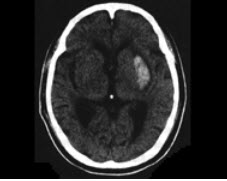

患者,男,70岁,有高血压病史10年,晨起大便时突发头痛,右侧肢体无力1天入院。体查:血压190/110mmHg,神志清楚,右侧鼻唇沟浅,伸舌偏右,右侧肌力4级。脑CT见如图所示病灶。

(单选题)该患者最可能的诊断是( )

A:脑出血

B:短暂性脑缺血发作

C:脑栓塞

D:脑血栓形成

E:蛛网膜下隙出血

第2题,共2个问题

(单选题)该病灶为哪根血管病变所致( )

A:大脑中动脉主干

B:脉络膜前动脉大脑

C:小脑后下动脉

D:丘脑穿通动脉

E:豆纹动脉